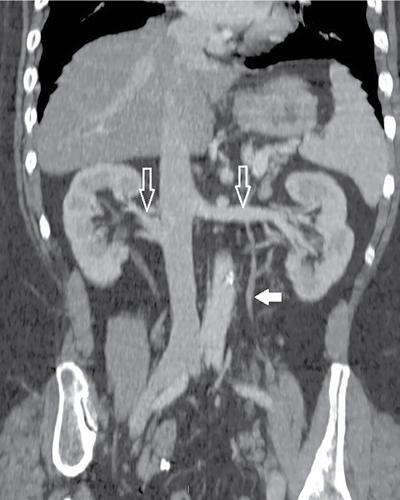

Amit Kumar Kamble, Abhinav Ranwaka The adult urinary system is formed of a pair of kidneys, a pair of ureters, a urinary bladder and a urethra. All these structures are extraperitoneal in location and extend from upper abdomen to the pelvis and into the exterior. These organs can be visualised on a host of imaging modalities, and a knowledge of these appearances helps the radiologist identify the relevant pathologies. Having a complex embryological development, the urinary system can have a wide spectrum of normal and abnormal anatomical variants. This chapter describes the appearance of the urinary system in commonly used imaging modalities and their common variants. Kidneys are paired bean-shaped structures situated in the retroperitoneum on either side of the vertebral column. The kidney consists of The renal sinus contains: The kidneys are surrounded by the renal capsule which is enclosed in the perirenal space. This space predominantly contains the perinephric fat and has thin septations within (Kunin’s septa); these septae may be thickened in various renal pathologies seen as perinephric stranding on imaging. The perirenal space is bounded by the perirenal fasciae, called the Gerota fascia (anterior perirenal fascia) and Zuckerkandl fascia (posterior perirenal fascia). The leaves of perirenal fascia fuse superiorly, laterally and medially. Superiorly, the perirenal fasciae also enclose the adrenal gland, which is separated from the kidney by a septum (Fig. 10.2.2). The anterior and posterior perirenal fasciae fuse laterally to form the lateral conal fascia. Medially, the perirenal fascia also encloses the renal pedicle. Medially, it communicates with renal sinus fat. There may be the communication of perirenal spaces across the midline. Superiorly, the perirenal space communicates with the bare area of the liver or spleen. The ureter arises from the perirenal space and travels inferiorly in anterior pararenal space. Inferiorly, the perinephric space may communicate with periureteric tissues. Interfascial planes are potential planes in between the leaves of the anterior perirenal fascia, called the retromesenteric plane and in the anterior perirenal fascia called the retrorenal plane. Anterior pararenal space: It is bounded by parietal peritoneum anteriorly, anterior perirenal fascia (Gerota) posteriorly and lateral conal fascia laterally. The anterior pararenal space contains the pancreas, second and third part of the duodenum, the retroperitoneal segments of ascending and descending colon and the roots of the small bowel mesentery and transverse mesocolon. Posterior pararenal space: It is bounded by posterior perirenal fascia (Zuckerkandl) anteriorly, fascia transversalis posteriorly and lateral conal fascia laterally. Caudally, the pararenal spaces communicate with each other and also with the extraperitoneal spaces. All the three spaces communicate at the pelvic brim. Understanding of the anatomy of spaces around the kidney is important for local staging of renal pathologies. Renal arteries are the branches of abdominal aorta. They originate laterally from the aorta below the origin of superior mesenteric artery. Accessory unilateral renal artery occurs in 30% of the population and bilaterally in 10% of population. Renal artery is divided into anterior division, which divides into four segmental branches and a posterior division; these arteries are end arteries supplying the respective segments of the kidneys (Fig. 10.2.3): apical, upper, middle, lower segments supplied by the anterior division, and a posterior segment supplied by the posterior division. The segmental arteries divide into lobar branches one to each to renal pyramid. Before reaching to pyramid, they divide into two to three interlobar branches. At the junction of cortex and medulla, interlobar arteries divide into arcuate arteries at the right angle. They further subdivide into interlobular artery, afferent and efferent arterioles. The efferent arteriole drains into peritubular plexus. The plane where the branches of the anterior and posterior divisions meet is located between the anterior two-thirds and posterior one-third of the kidney and is relatively avascular; it is called the avascular plane of Brodel (Fig. 10.2.3), and is a relatively safe site for nephrostomy access. Peritubular plexus converges to form the interlobular vein. These veins accompany their arterial counterparts and drain into the renal vein. The renal veins are situated anteriorly to the renal arteries and finally drain into the inferior vena cava at the right angles (Fig. 10.2.4). The two left renal veins may be present one passing anterior and other posterior to the aorta known as persistence of renal collar. Sometimes a single retroaortic left renal vein (Fig. 10.2.5) may be present. Supernumerary right renal vein may be seen. Renal vein variations are more common on the right side. The lymphatics of the kidneys drain into the lateral aortic nodes at the level of origin of renal arteries. Normal kidneys may be visualised on a frontal abdominal radiograph as faint oval shadows on either side of the vertebral column immediately besides the psoas shadows (Fig. 10.2.6). On contrast radiography and intravenous urography, the renal shadows show gradual opacification, peaking between 30 and 60 seconds followed by opacification of the pelvicalyceal system on subsequent radiographs. The kidneys are visualised in longitudinal and transverse views usually by placing the probe in the loin with the patient in supine or lateral position. The normal kidneys appear less echogenic than the liver and show a thin echogenic capsule. The surface of the kidney is usually smooth in adults, and may be lobulated in infants and young children. The renal parenchyma shows an outer cortex, which generally shows a uniform thickness, surrounding the less echogenic medullary pyramids, with invaginations of the columns of Bertin between the medullary pyramids (Fig. 10.2.7). This differentiation between the echogenicity of the cortex and medulla is called corticomedullary differentiation, which is lost in certain disease states. The renal pyramids are most hypoechoic compared in infancy gradually becoming less hypoechoic with age. The hypoechoic renal pyramids may at times be confused for hydronephrosis by an inexperienced observer. Arcuate arteries may be identified in some adults between the cortex and medulla as linear echogenic lines (Fig. 10.2.8A) and should not be mistaken for calculi. The renal sinus is seen as a central hyperechoic area of the kidneys owing to the presence of fat. The renal calyces and pelvis are not visualised normally as they are collapsed. They may sometimes be seen if the bladder is overdistended, a finding which reverses once the patient emptied the bladder. Doppler interrogation allows evaluation of the renal vasculature in great detail. The renal artery, its segmental, interlobular and arcuate branches and the corresponding veins can be easily visualised (Fig. 10.2.8B). At the renal hilum, the renal vein lies anterior to the renal artery. The right renal artery is longer and lies posterior to the inferior vena cava (IVC). The left renal vein crosses midline and courses in between the aorta and superior mesenteric artery. On CT scan (Fig. 10.2.9), the kidneys are well identified and well demarcated owing to the presence of surrounding fat. They show a homogeneous appearance with intermediate density between 35 and 55 HU on non-contrast CT scan with a central low-density renal sinus.